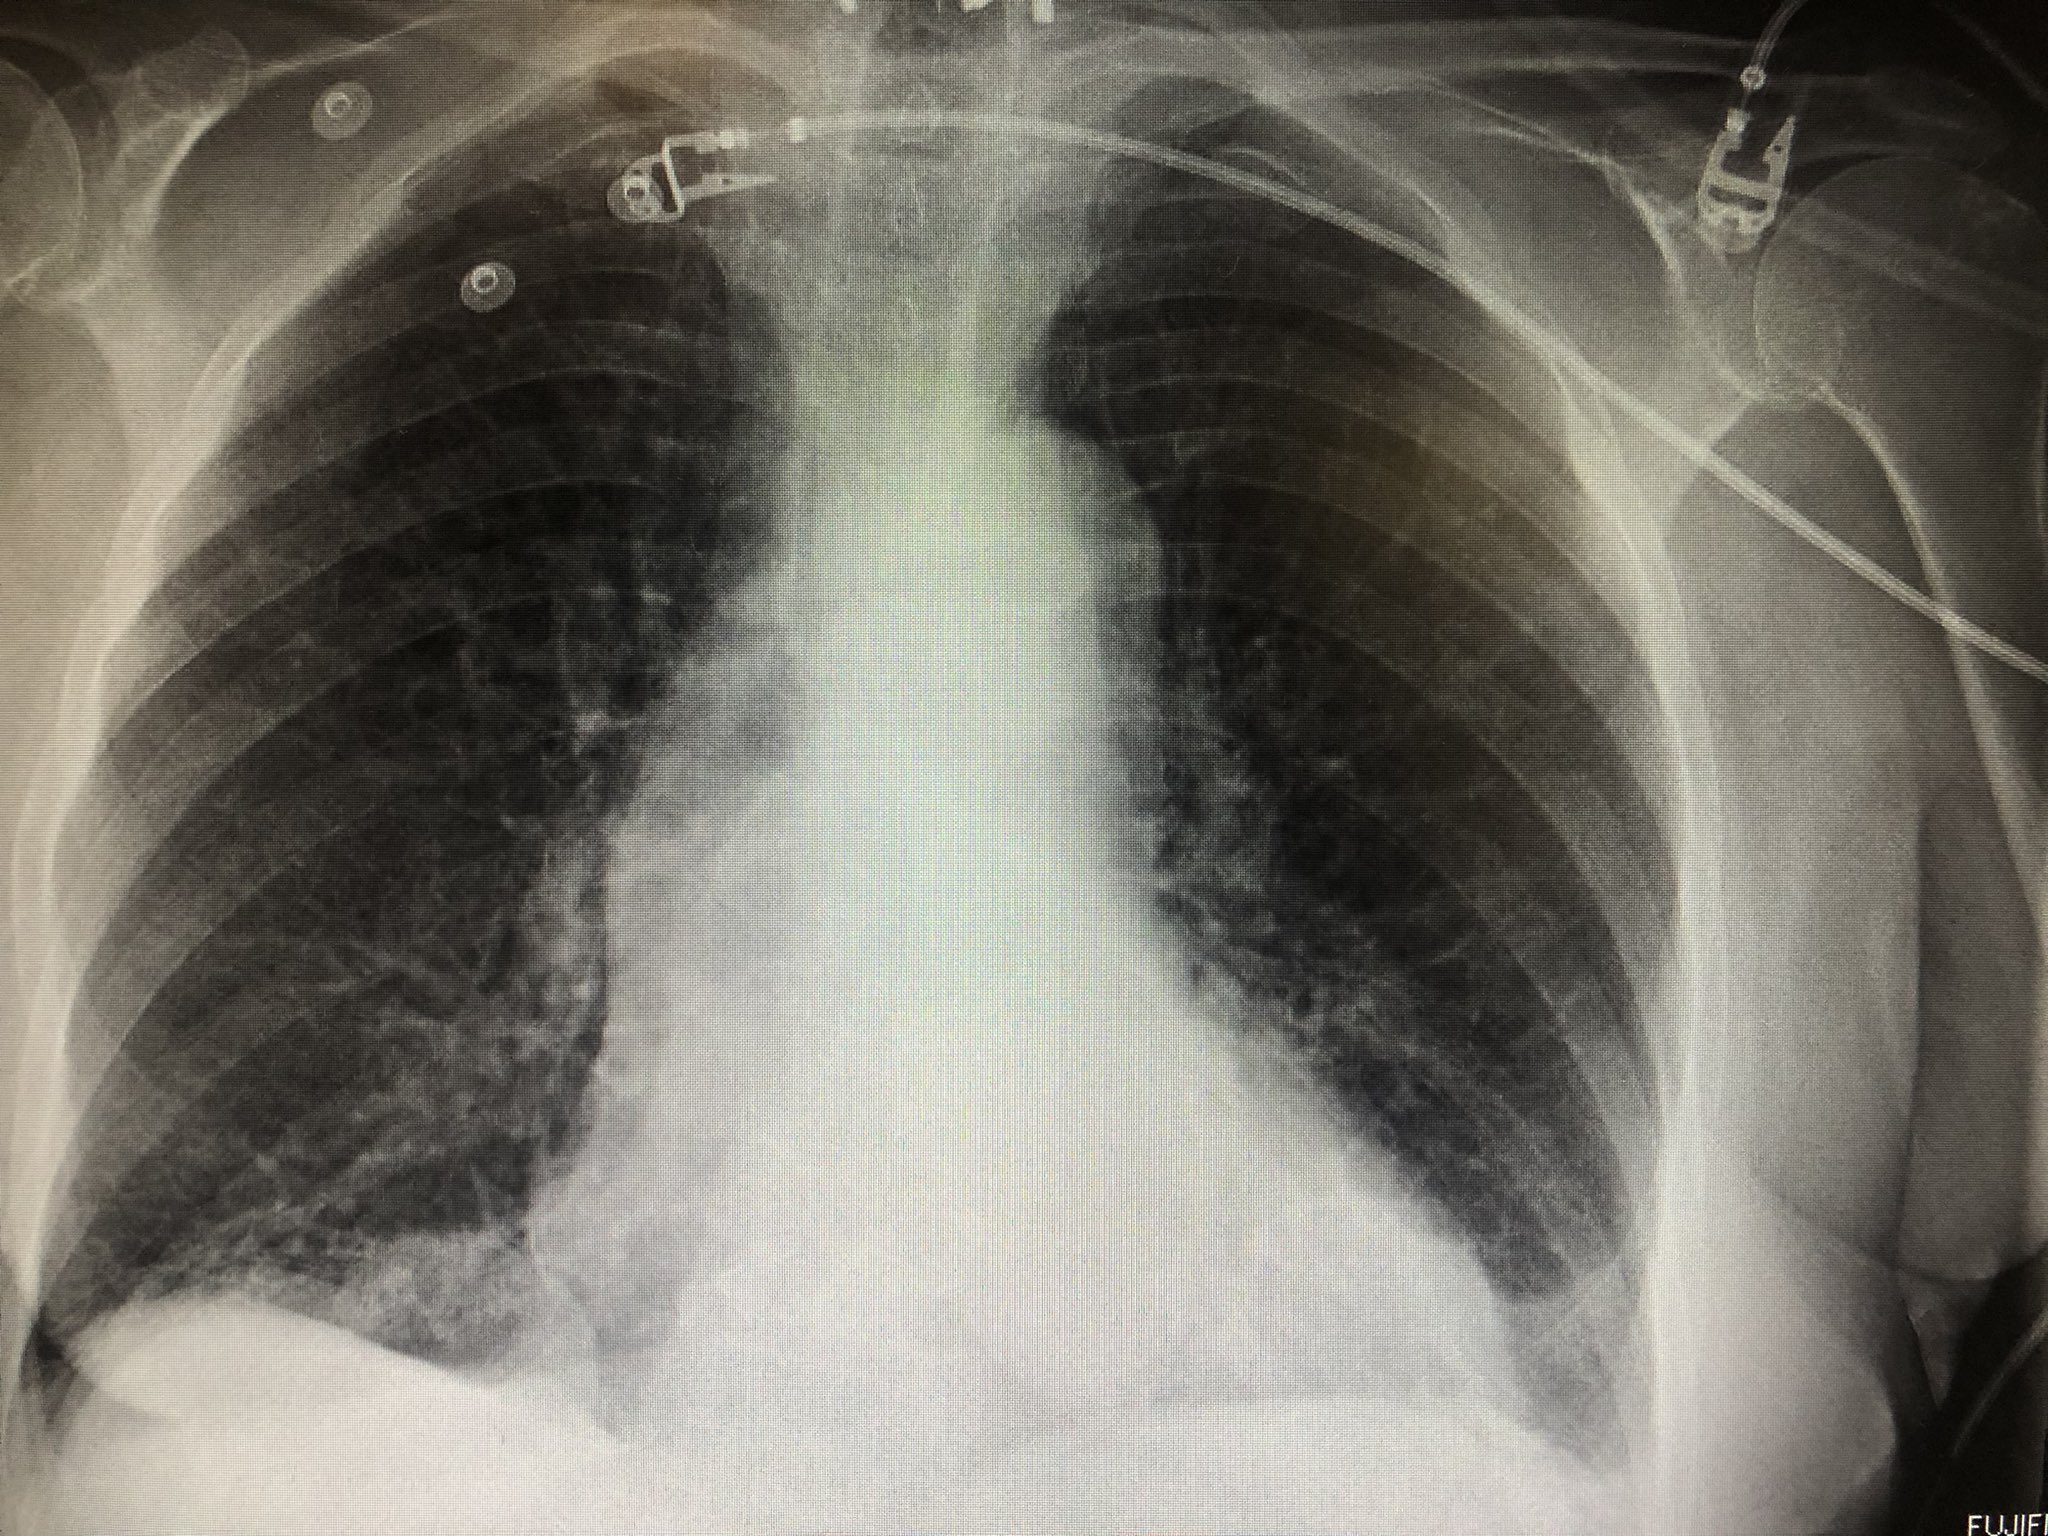

Chest radiograph showing enlarged cardiac silhouette and bibasilar Chest X Ray Bibasilar Atelectasis Each approach aims to help identify possible underlying causes together with other. Atelectasis is a radiopathological sign that can be categorized in many ways. Atelectases) refers to the collapse or incomplete expansion of pulmonary parenchyma. It happens when tiny air sacs within the lung, called alveoli, lose air. Atelectasis may be used synonymously with. Atelectasis is one of the most. Chest X Ray Bibasilar Atelectasis.

Chest Xray showing bibasilar airspace opacities and cardiomegaly Chest X Ray Bibasilar Atelectasis It happens when tiny air sacs within the lung, called alveoli, lose air. But other tests may be done to. Atelectasis is one of the most common breathing complications after surgery. Each approach aims to help identify possible underlying causes together with other. Atelectasis may be used synonymously with. Atelectases) refers to the collapse or incomplete expansion of pulmonary parenchyma.. Chest X Ray Bibasilar Atelectasis.